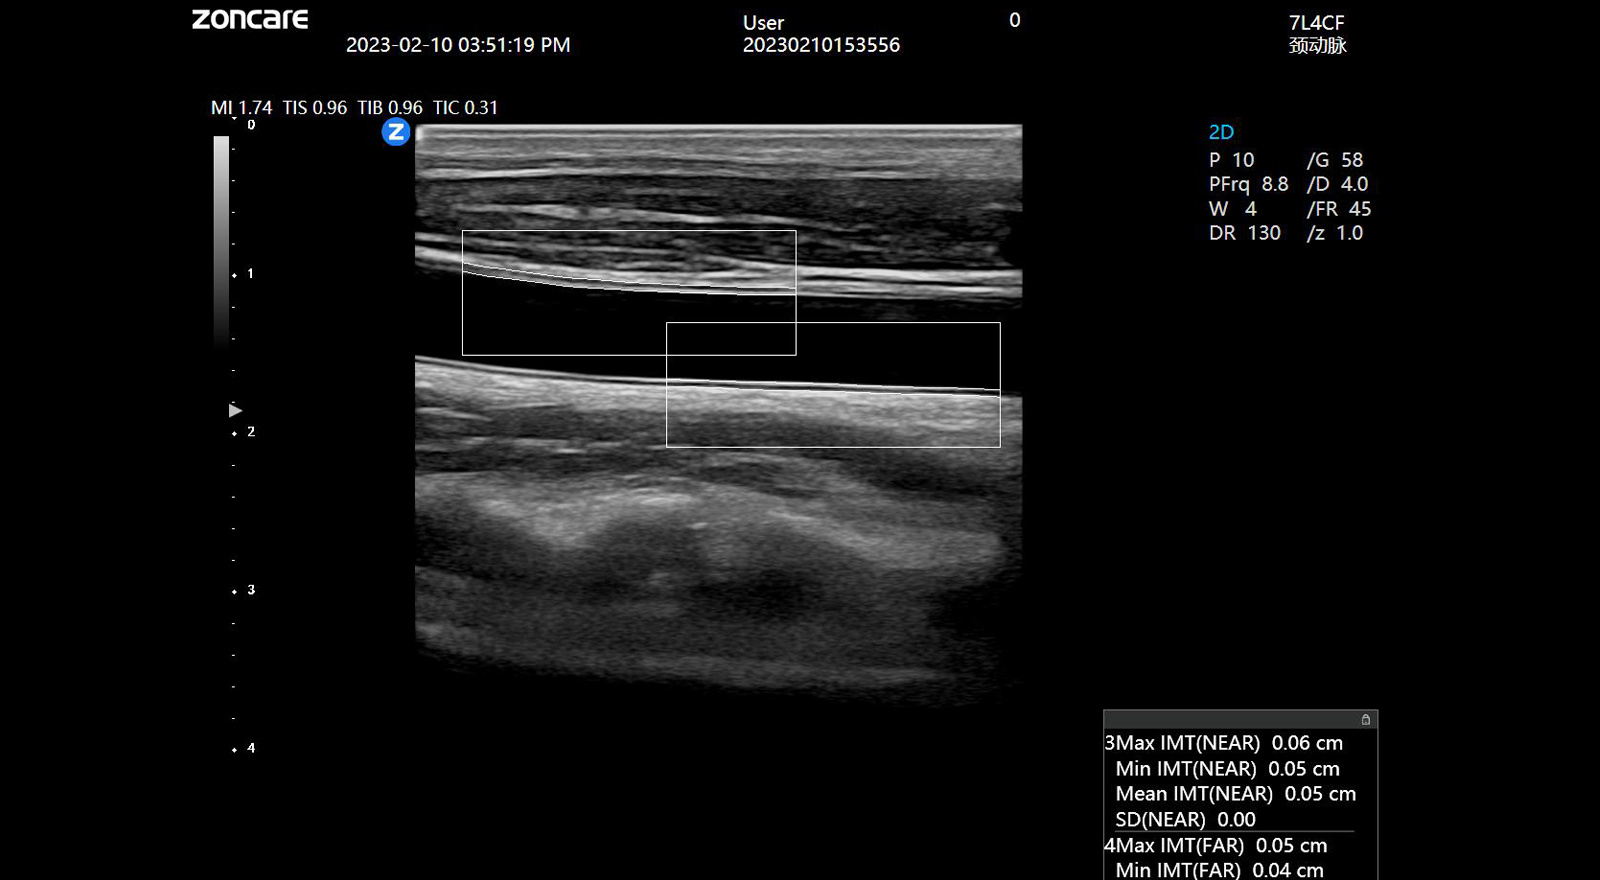

血管内中膜厚度自动测量 IMT

可以自动识别并自动测量血管内中膜的厚度,提供内中膜厚度测量报告,为心脑血管事件的预防提供评估指标